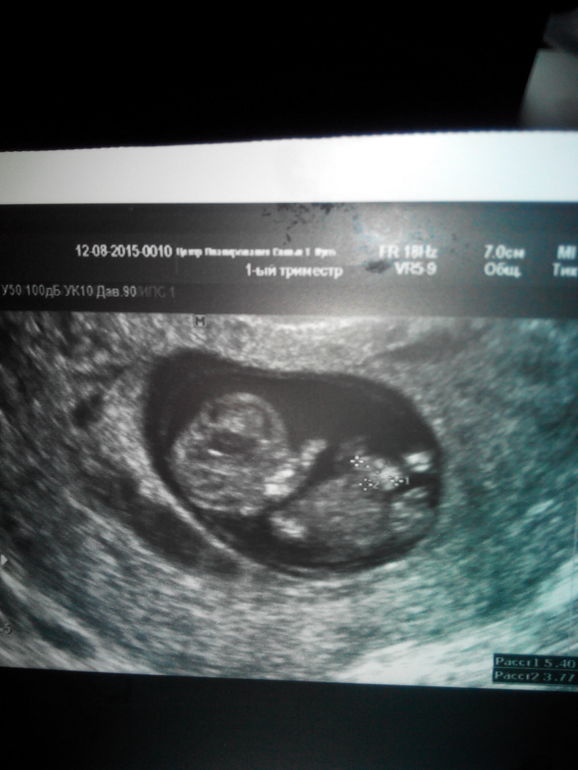

Вот мы увидели нашего карапузика)

Вопросы про УЗИ, обследования и анализы: что, где, как, когда? сегодня 11н2д

по узи как и в 7 недель,было 6, так и сейчас 10..

Сказали прийти на скрининг через 2 недели..

25го на кровь, 27 на узи с высислениями риска..

по узи ни отслойки ,ни угрозы, все хорошо)

и еще) прежположительно сказала пол, говорит 75%,что девочка)